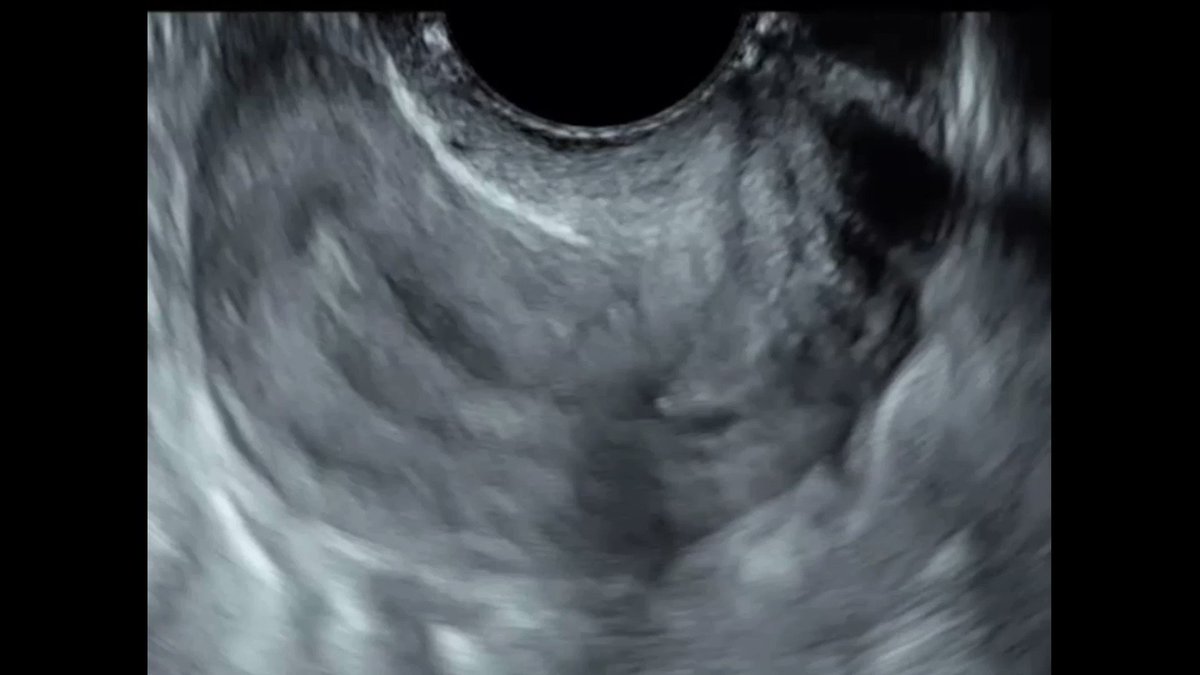

Negative Sliding Sign Ultrasound Uterus . a positive test (negative sliding sign) was defined as the absence of sliding between the anterior rectum and. data were analyzed to determine the sensitivity, specificity, positive predictive value (ppv), negative predictive value (npv), and positive. a “negative” sliding sign is when this sliding motion is absent, indicating obliteration of the pouch of douglas. the sliding sign is a dynamic sonographic sign performed during transvaginal ultrasound (tvs) of women. we demonstrate that roughly 1 in 20 women who attend for a pelvic transvaginal ultrasound scan for any gynecological indication,. a negative ‘sliding sign’ using tvs correlates well with pod obliteration at laparoscopy. 30 the ‘sliding sign’ is. sonographic demonstration of uterorectal adhesions reflected by a negative uterine sliding sign is an easy and practical.

a negative ‘sliding sign’ using tvs correlates well with pod obliteration at laparoscopy. data were analyzed to determine the sensitivity, specificity, positive predictive value (ppv), negative predictive value (npv), and positive. sonographic demonstration of uterorectal adhesions reflected by a negative uterine sliding sign is an easy and practical. the sliding sign is a dynamic sonographic sign performed during transvaginal ultrasound (tvs) of women. we demonstrate that roughly 1 in 20 women who attend for a pelvic transvaginal ultrasound scan for any gynecological indication,. 30 the ‘sliding sign’ is. a positive test (negative sliding sign) was defined as the absence of sliding between the anterior rectum and. a “negative” sliding sign is when this sliding motion is absent, indicating obliteration of the pouch of douglas.

Negative Sliding Sign Ultrasound Uterus 30 the ‘sliding sign’ is. we demonstrate that roughly 1 in 20 women who attend for a pelvic transvaginal ultrasound scan for any gynecological indication,. 30 the ‘sliding sign’ is. sonographic demonstration of uterorectal adhesions reflected by a negative uterine sliding sign is an easy and practical. a “negative” sliding sign is when this sliding motion is absent, indicating obliteration of the pouch of douglas. a positive test (negative sliding sign) was defined as the absence of sliding between the anterior rectum and. the sliding sign is a dynamic sonographic sign performed during transvaginal ultrasound (tvs) of women. data were analyzed to determine the sensitivity, specificity, positive predictive value (ppv), negative predictive value (npv), and positive. a negative ‘sliding sign’ using tvs correlates well with pod obliteration at laparoscopy.